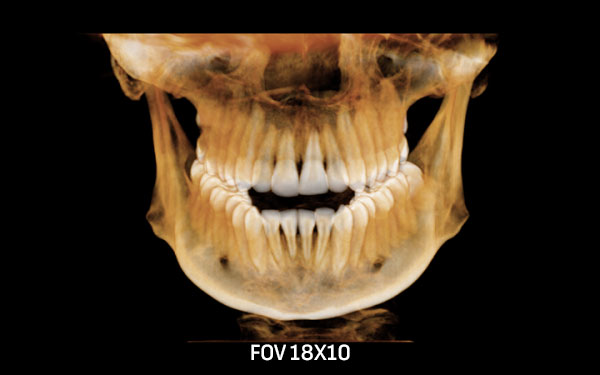

2D и 3D CBCT РТГ ДИГИТАЛНА ДИЈАГНОСТИКА

За точна дијагноза и третман насочен кон целта, потребно е да се погледне во внатрешноста на забот. За таа цел нудиме широк спектар на опции за оваа намена.

Преку нашите истражувачки активности, нашиот тим е запознаен со најновите научни наоди и може да ги исполни највисоките технолошки и професионални очекувања. За прегледи и проценки, имаме широк спектар на опции. Користиме различни методи за сликање, како што се проекциона радиографија, томографија и компјутерска томографија.

Kористиме најнова технологија за да овозможиме прецизен третман за нашите пациенти преку методи на снимање.